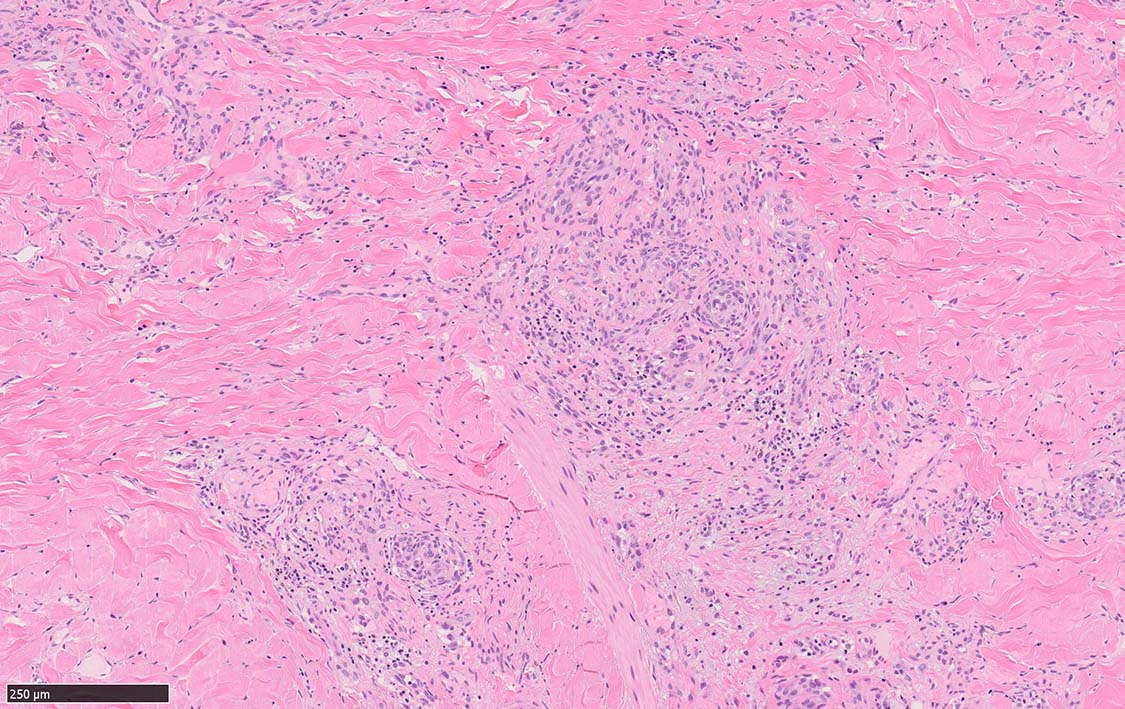

局面状病変の病理

病変は真皮から皮下脂肪織に及ぶようになり, 血管内皮様細胞による新生管腔の増加と拡張, 浮腫が著明になる. 赤血球漏出やヘモジデリン貪食細胞もめだつようになる.

膠原線維間に紡錘形細胞が増生してくる.

結節性病変の形成

紡錘形細胞が著しく増生し束状に走行する部分と, 内皮細胞様細胞による多数の小管腔構造が巣状にひろがり, 一見, 線維腫と血管腫が混在しているように見える. 一部の症例を除き, これらの増生細胞は異型性に乏しいことが多い.

細血管周囲に血管内皮様の紡錘形細胞が増生, 一部に赤血球をいれた裂隙の形成がある. 細胞の異型はみられず, mitosisの増多もない. hemosiderin-laden macrophageが散在する.

病変は真皮内に現局している. 初期斑状病変に相当すると考えられる. 本例では, 特徴とされる形質細胞浸潤増加はみられない.

参考症例:中部交見会1246: Kaposi's sarcoma 右足内側部皮膚/ 40歳代男性 焼津市立病院 久力 権先生